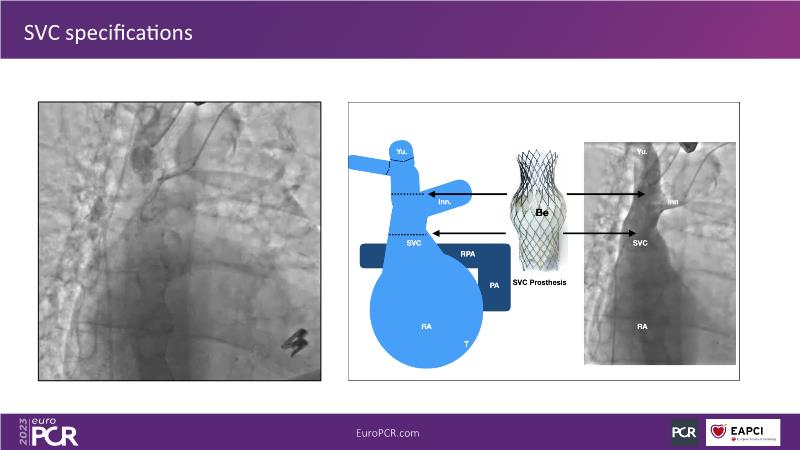

Heterotopic valve replacement for patients with right heart failure and tricuspid regurgitation - All you need to know!

Discover the comprehensive guide to heterotopic valve replacement for patients experiencing right heart failure and tricuspid regurgitation. Join this session to gain insights into patient selection criteria, delve into the concept behind this innovative procedure, and grasp the fundamental aspects of its execution.

- To understand the basics of the procedure